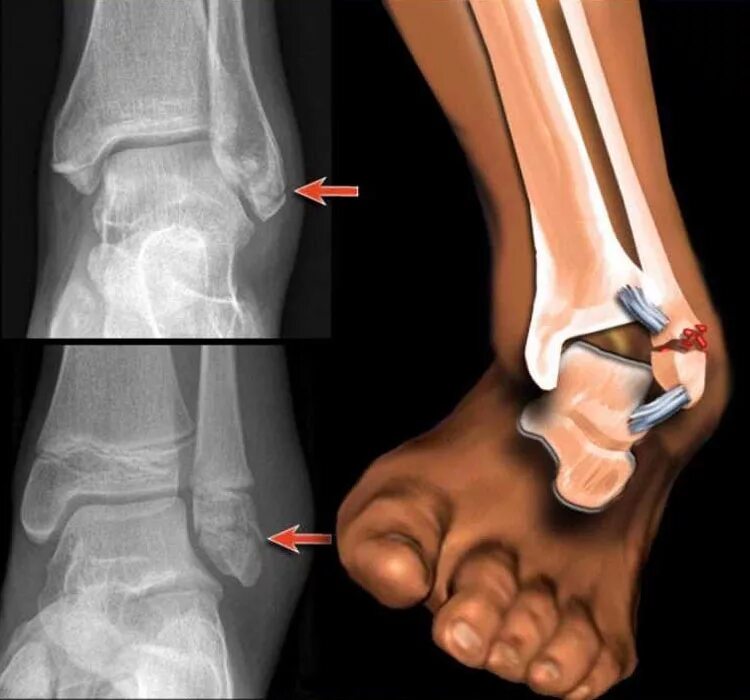

Растяжение связок голеностопа как долго